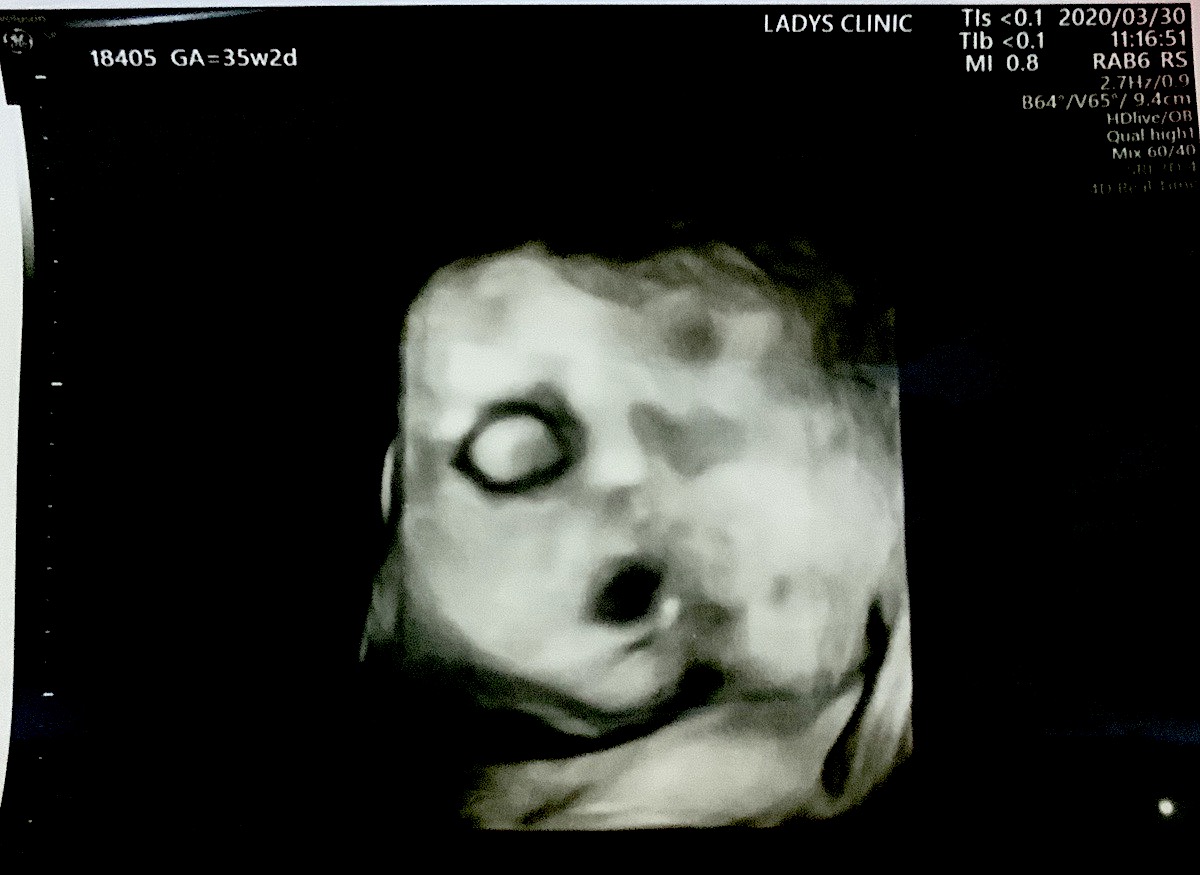

妹が嬉しそうにエコー写真持ってきたので見せてもらった。とんでもない悪魔を産もうとしているのかもしれない